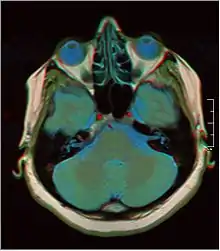

![]() Cross-sectional T1-weighted MRI of a healthy human brain acquired with an ultra high-field MR of 7 Tesla field strength  | |

Magnetic resonance imaging of the brain uses magnetic resonance imaging (MRI) to produce high quality two-dimensional or three-dimensional images of the brain and brainstem as well as the cerebellum without the use of ionizing radiation (X-rays) or radioactive tracers.